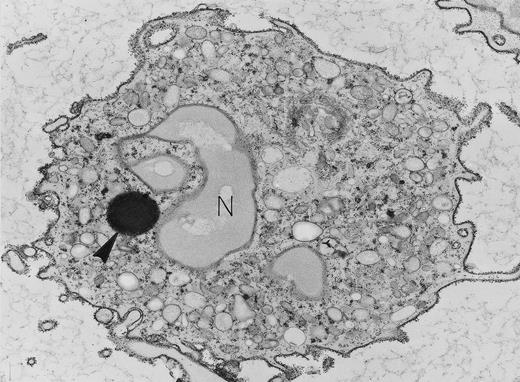

Neutrophil with lipid body. Specialized ultrastructural procedures were used to image this peripheral blood neutrophil. A reduced osmium postfixation step renders nuclear lobes (N) and secretory granules poorly electron-dense but each individual particle of cytoplasmic glycogen is electron-dense, and the single, large, round, membrane-free lipid body (arrowhead) is highly electron-dense. Exposure to cationized ferritin after fixation has provided a uniform layer of electron-dense ferritin particles bound to the plasma membrane. Original magnification × 8,000. (Courtesy of Ann M. Dvorak, MD, Department of Pathology, Beth Israel Hospital, Harvard Medical School, 330 Brookline Ave, Boston, MA 02215.)